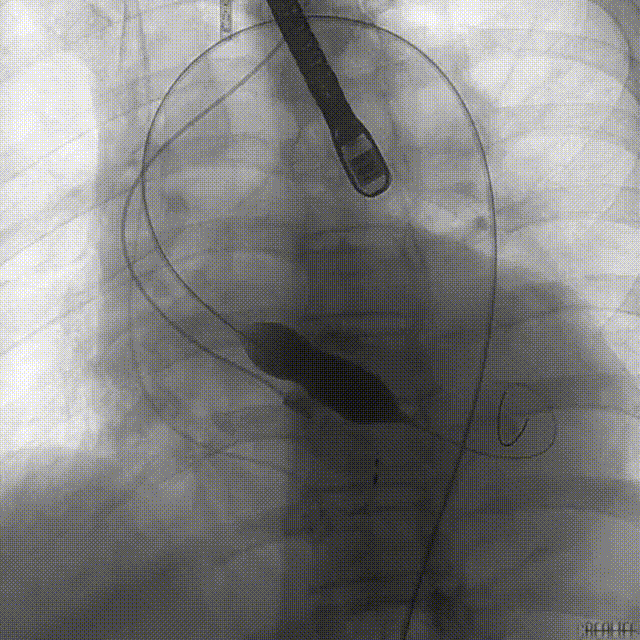

手术采用全麻配合食道超声,经右侧股动脉为主入路,得益于术者丰富经验,配合Evolut PRO优良的过弓性能及精准的器械跟踪性能,瓣膜系统很快到达预期位置。

球囊预扩张

递送到达释放位

因患者自身主动脉根部结构特殊,导致定位困难:严重的钙化灶使得猪尾导管很难送至窦底;但凭借Evolut PRO稳定的多次可回收功能,术者通过对瓣膜的回收及再释放,最终找到最佳释放位置,获得最佳疗效。

瓣膜释放